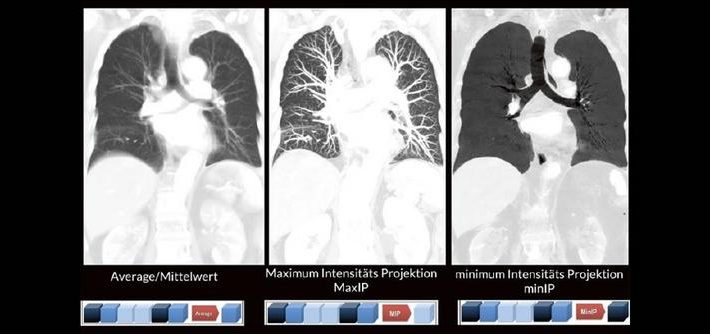

Bildnachverarbeitung in der CT (Webinar | Online)

Alex Riemer Moderne CT-Scanner unterstützen die Anwenderinnen und Anwender bei der Durchführung der meisten CT-Untersuchungen. Hierzu zählt auch das automatische Erstellen von streng coronalen und sagittalen Multiplanaren Reformatierungen (MPR´s). Es gibt jedoch CT-Untersuchungen, bei denen die MPR´s individuell an die Anatomie angepasst werden müssen. Doch gerade bei diesen Bildnachverarbeitungen gibt es oft Unsicherheiten darüber, worauf […]